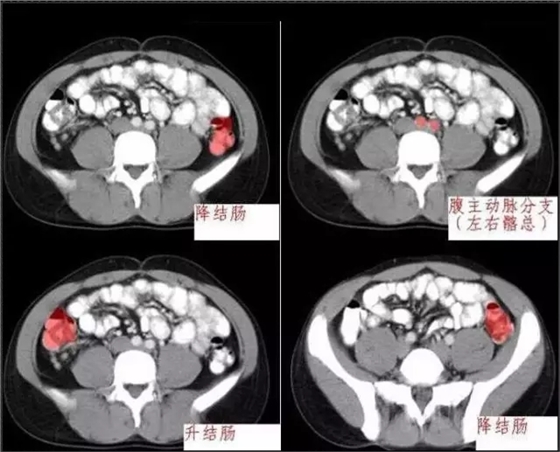

秒懂:腹部 CT 看這篇就夠